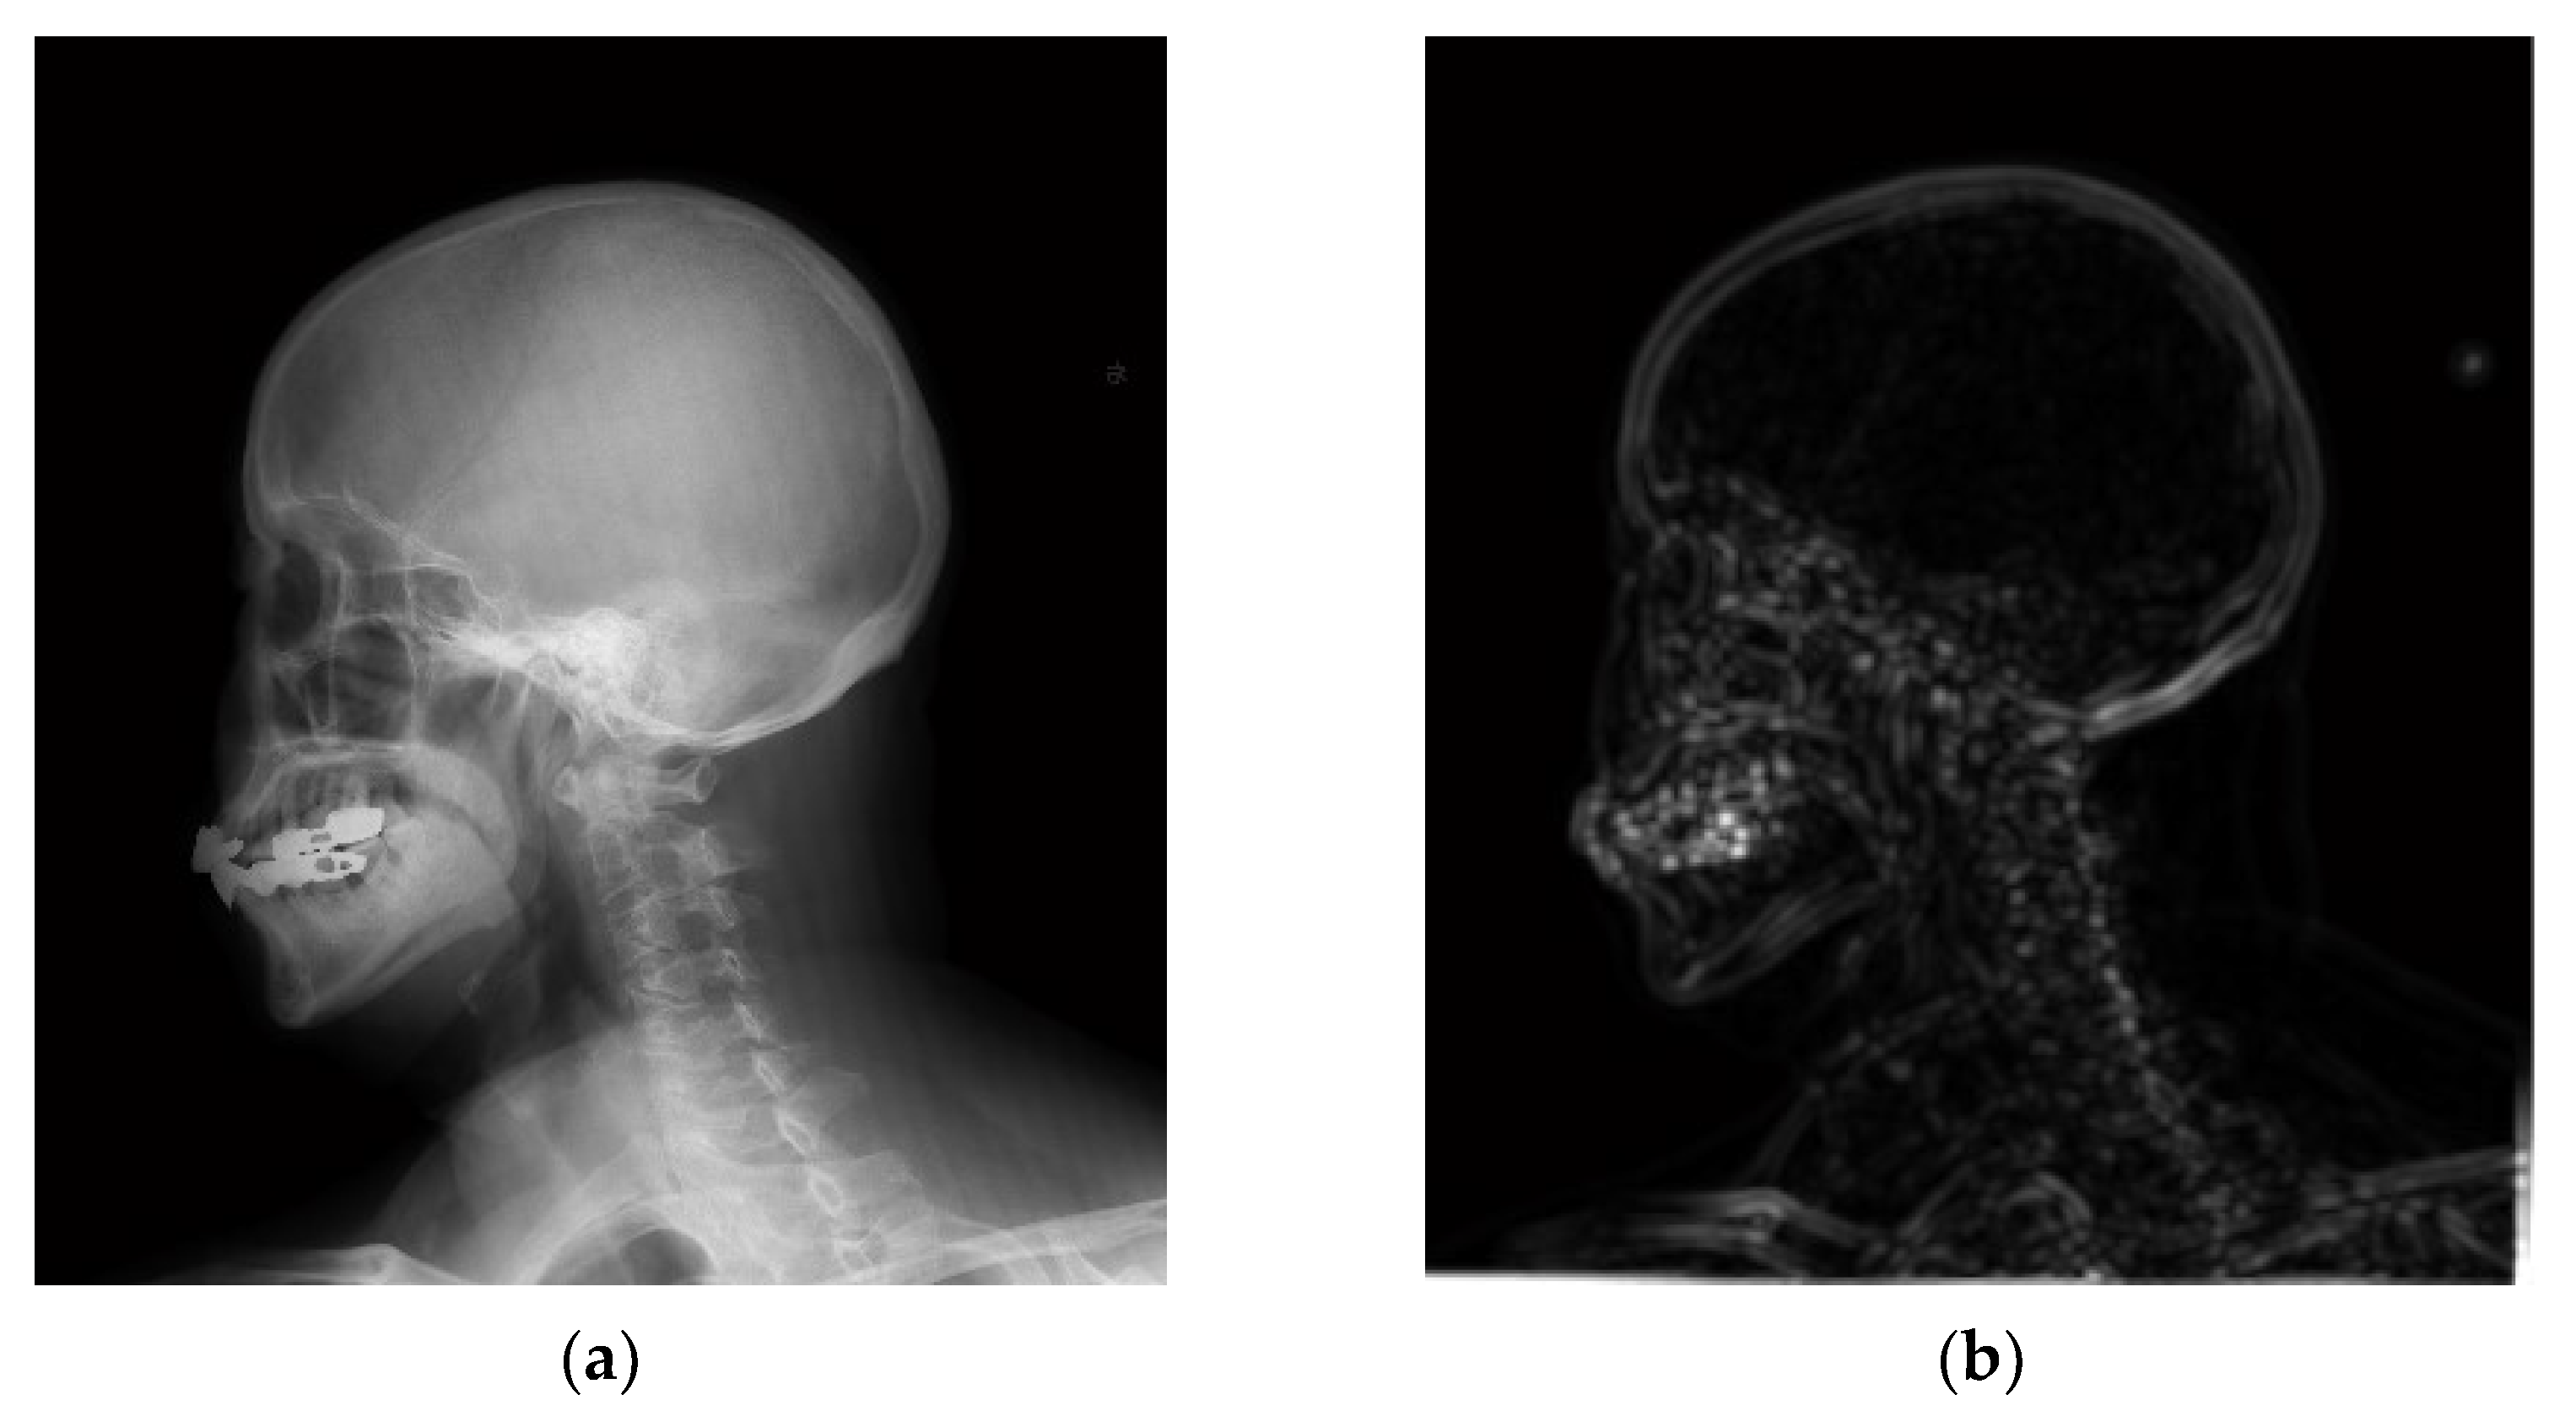

4.2. Simulations for Multiscale Noise Reduction in DR Images